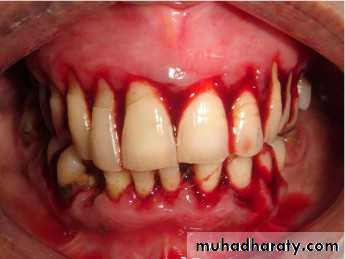

* Platelet defects :

a. Defect in the number of platelets( thrombocytopenia ).

b. Defect in the function of platelets

( thrombosthenia)

* Causes of thrombocytopenia :

* Coagulation defects :

When there is deficiency of coagulation factors e.g. hemophilia A ( factor VIII deficiency) , hemophilia B ( factor IX deficiency ) , factor VII deficiency ..etc.

Coagulation defects can also occur secondary to systemic diseases like liver failure .